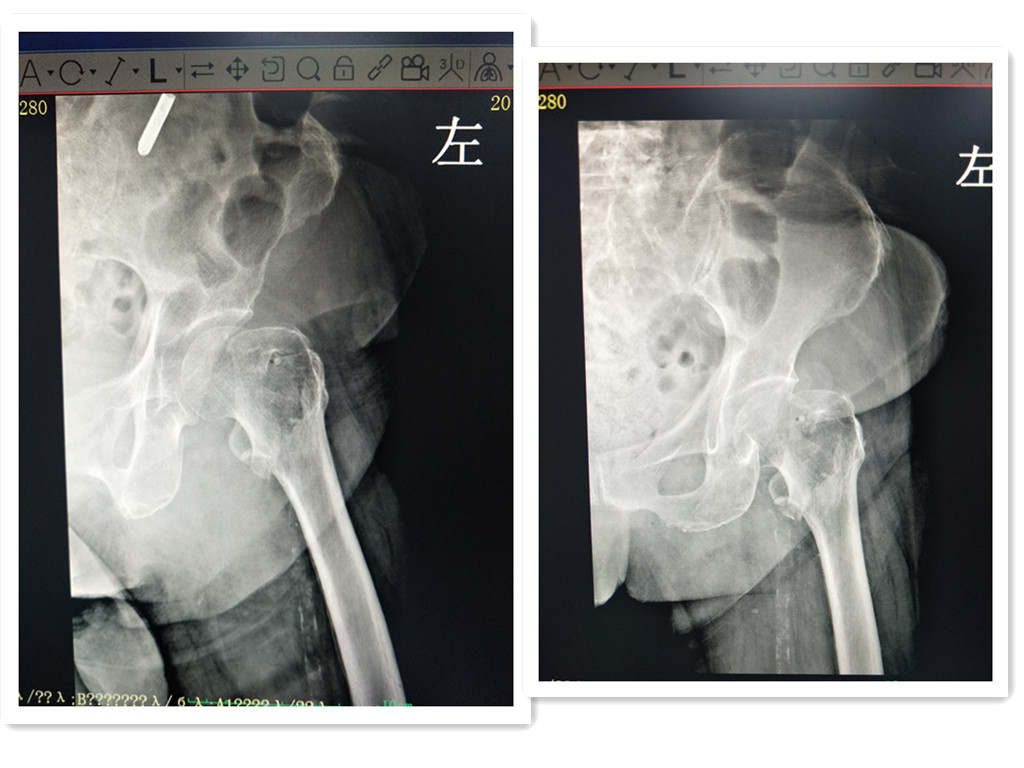

89岁高龄患者朱女士,因不慎跌倒致左髋部疼痛17小时,左下肢活动受限,活动时疼痛加剧,左下肢外旋畸形,左下肢纵向叩击痛(+)。广州东仁医院外二科专家接诊病人后对其病史进行了详细采集,了解到患者既往有高血压病史7年余,最高190/100mmHg,有2型糖尿病病史2年余,最高18.Ommo1/1,1年余前在它院确诊有冠状动脉粥样硬化性心脏病,20年前因车祸致左腕关节骨折。

入院后急查腰椎、髋关节、膝关节X膝线片:1、左侧骨粗隆间骨折。2、左膝关节退行性改变。3、腰椎退行性改变。诊断:1、左侧骨粗隆间骨折;2、高血压3级 很高危组;3、2型糖尿病;4、冠状动脉粥样硬化性心脏病;5、腰椎退行性改变;6、左膝关节退行性变。